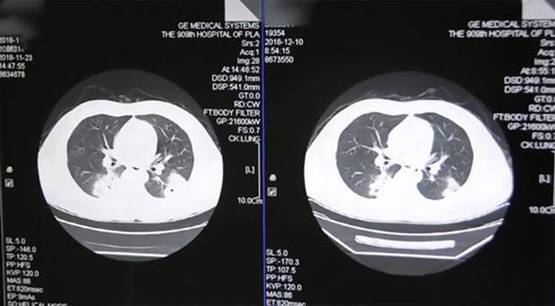

शुरुआत में डॉक्टरों के लगा कि पेंग को न्यूमोनिया है लेकिन इलाज के बाद भी उसके सिम्टम्पस दिखना जारी रहा. डॉक्टरों ने पेंग से फिर सू पूछताछ की और उसने बाद में बताया कि वह जिन मोजों को पहनता था, उन्हें सूंघता था.

फिजीशियन ने बाद में पाया कि शख्स को खतरनाक फंगल इन्फेक्शन हो चुका है. इसे पुलमोनरी फंगल डिसीज भी कहा जाता है. साइंस अलर्ट के मुताबिक, पेंग ने गंदे मोजों के फंगल स्पोर्स को सांस के जरिए अंदर ले लिया जिससे उसे इन्फेक्शन हो गया.

पल्मनोरी फंगल डिसीज या एस्पर्गिलोसिस की वजह से श्वसन प्रक्रिया पर बुरा असर पड़ता है लेकिन इसके लक्षण और परिणाम बहुत अलग-अलग होते हैं.

यह इन्फेक्शन फफूंदी की वजह से होता है. फफूंद घर के अंदर और बाहर हर जगह पाए जाते हैं. कमजोर इम्यून सिस्टम वाले लोगों पर फफूंद से होने वाले इन्फेक्शन का ज्यादा गंभीर असर पड़ता है. इन्फेक्शन के बाद सांस लेने में दिक्कत, खून वाली खांसी जैसे लक्षण सामने आते हैं.